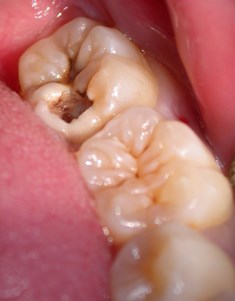

患者さんは20歳男性、訴えはは左下奥歯が何もしなくても痛いとの事。

所見としては左下一番奥の歯がものすごく

深い虫歯になっておりレントゲンでは神経にまで虫歯が達していると思われました。